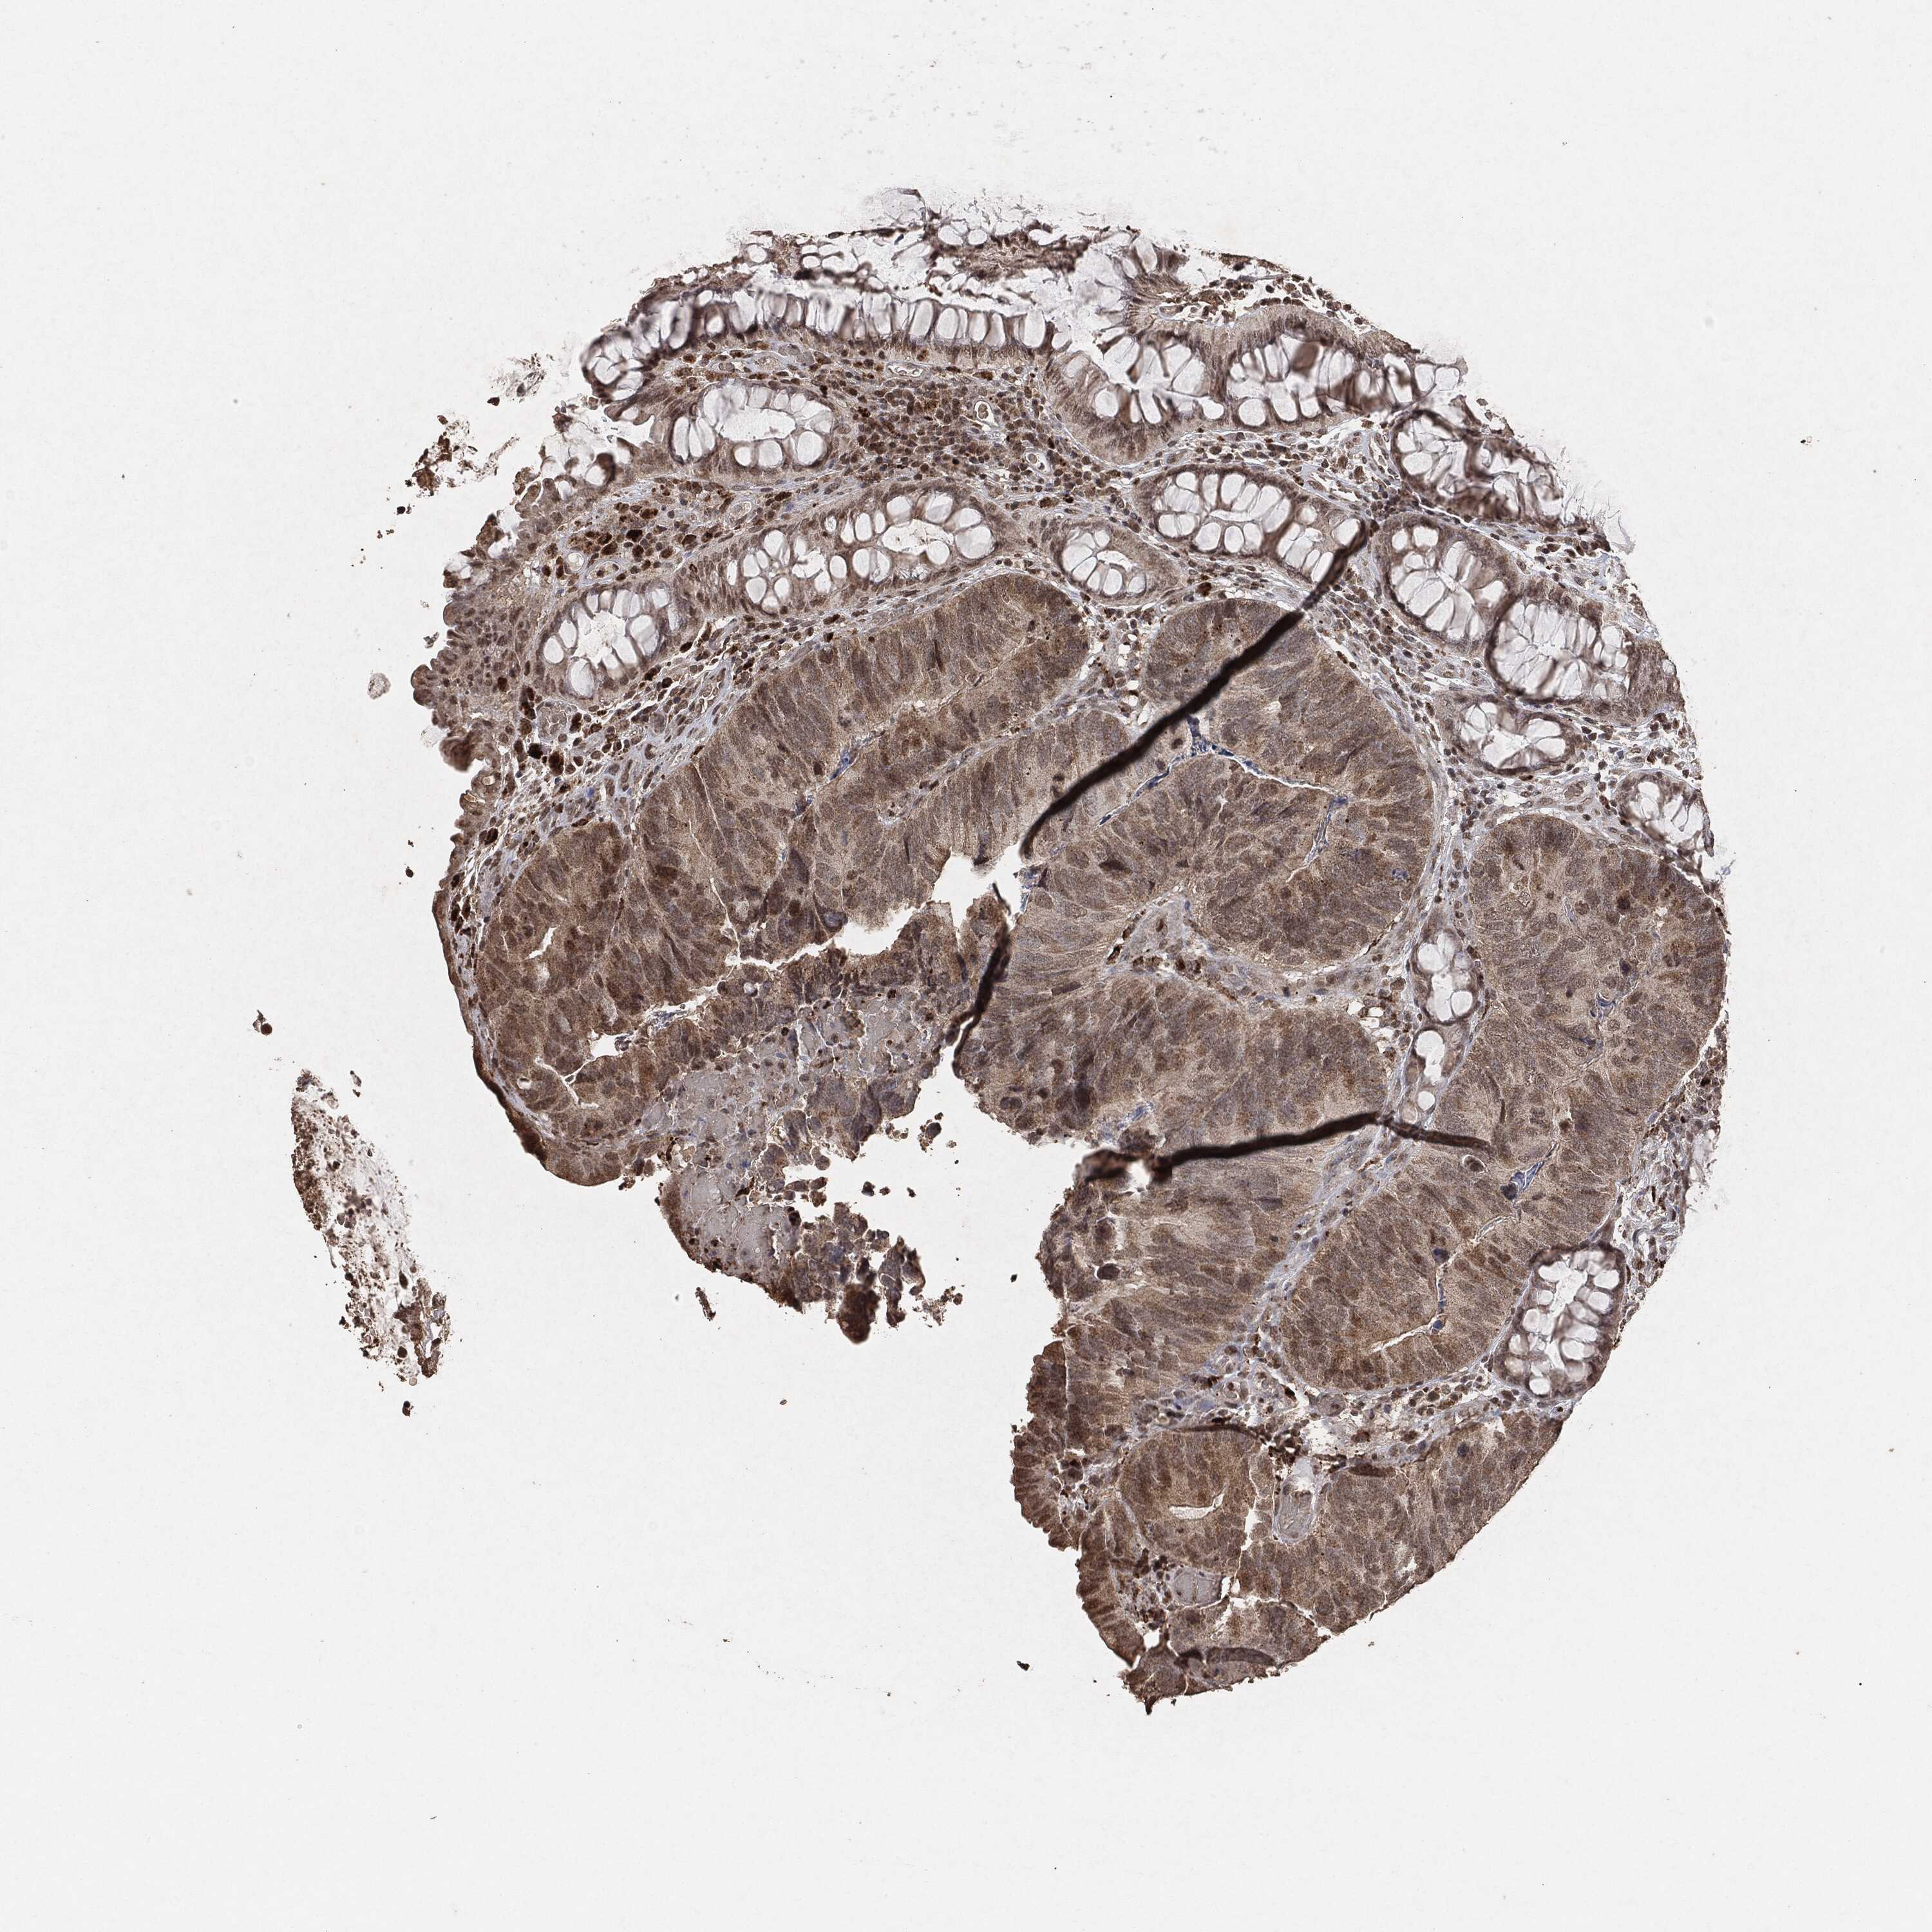

CANCER COLORECTAL CANCER Show tissue menu

Colorectal cancer

Human cancer

Colon adenocarcinoma